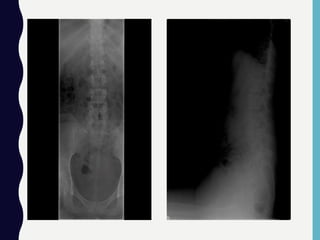

Gambar : Osteofit atau Spur Formation

Foto Lumbosakral :

• Allignment dan trabekulasi tulang normal

• Tidak tampak adanya fraktur corpus vertebrae

• Corpus vertebrae dan pedikel normal

• Diskus intervertebralis L4-L5 dan L5-S1 menyempit, diskus intervertebralis lainnya normal.

• Tampak osteofit pada vertebrae lumbal

Kesan : Suspect HNP L4-L5 dan L5-S1

Spondyloarthrosis lumbalis